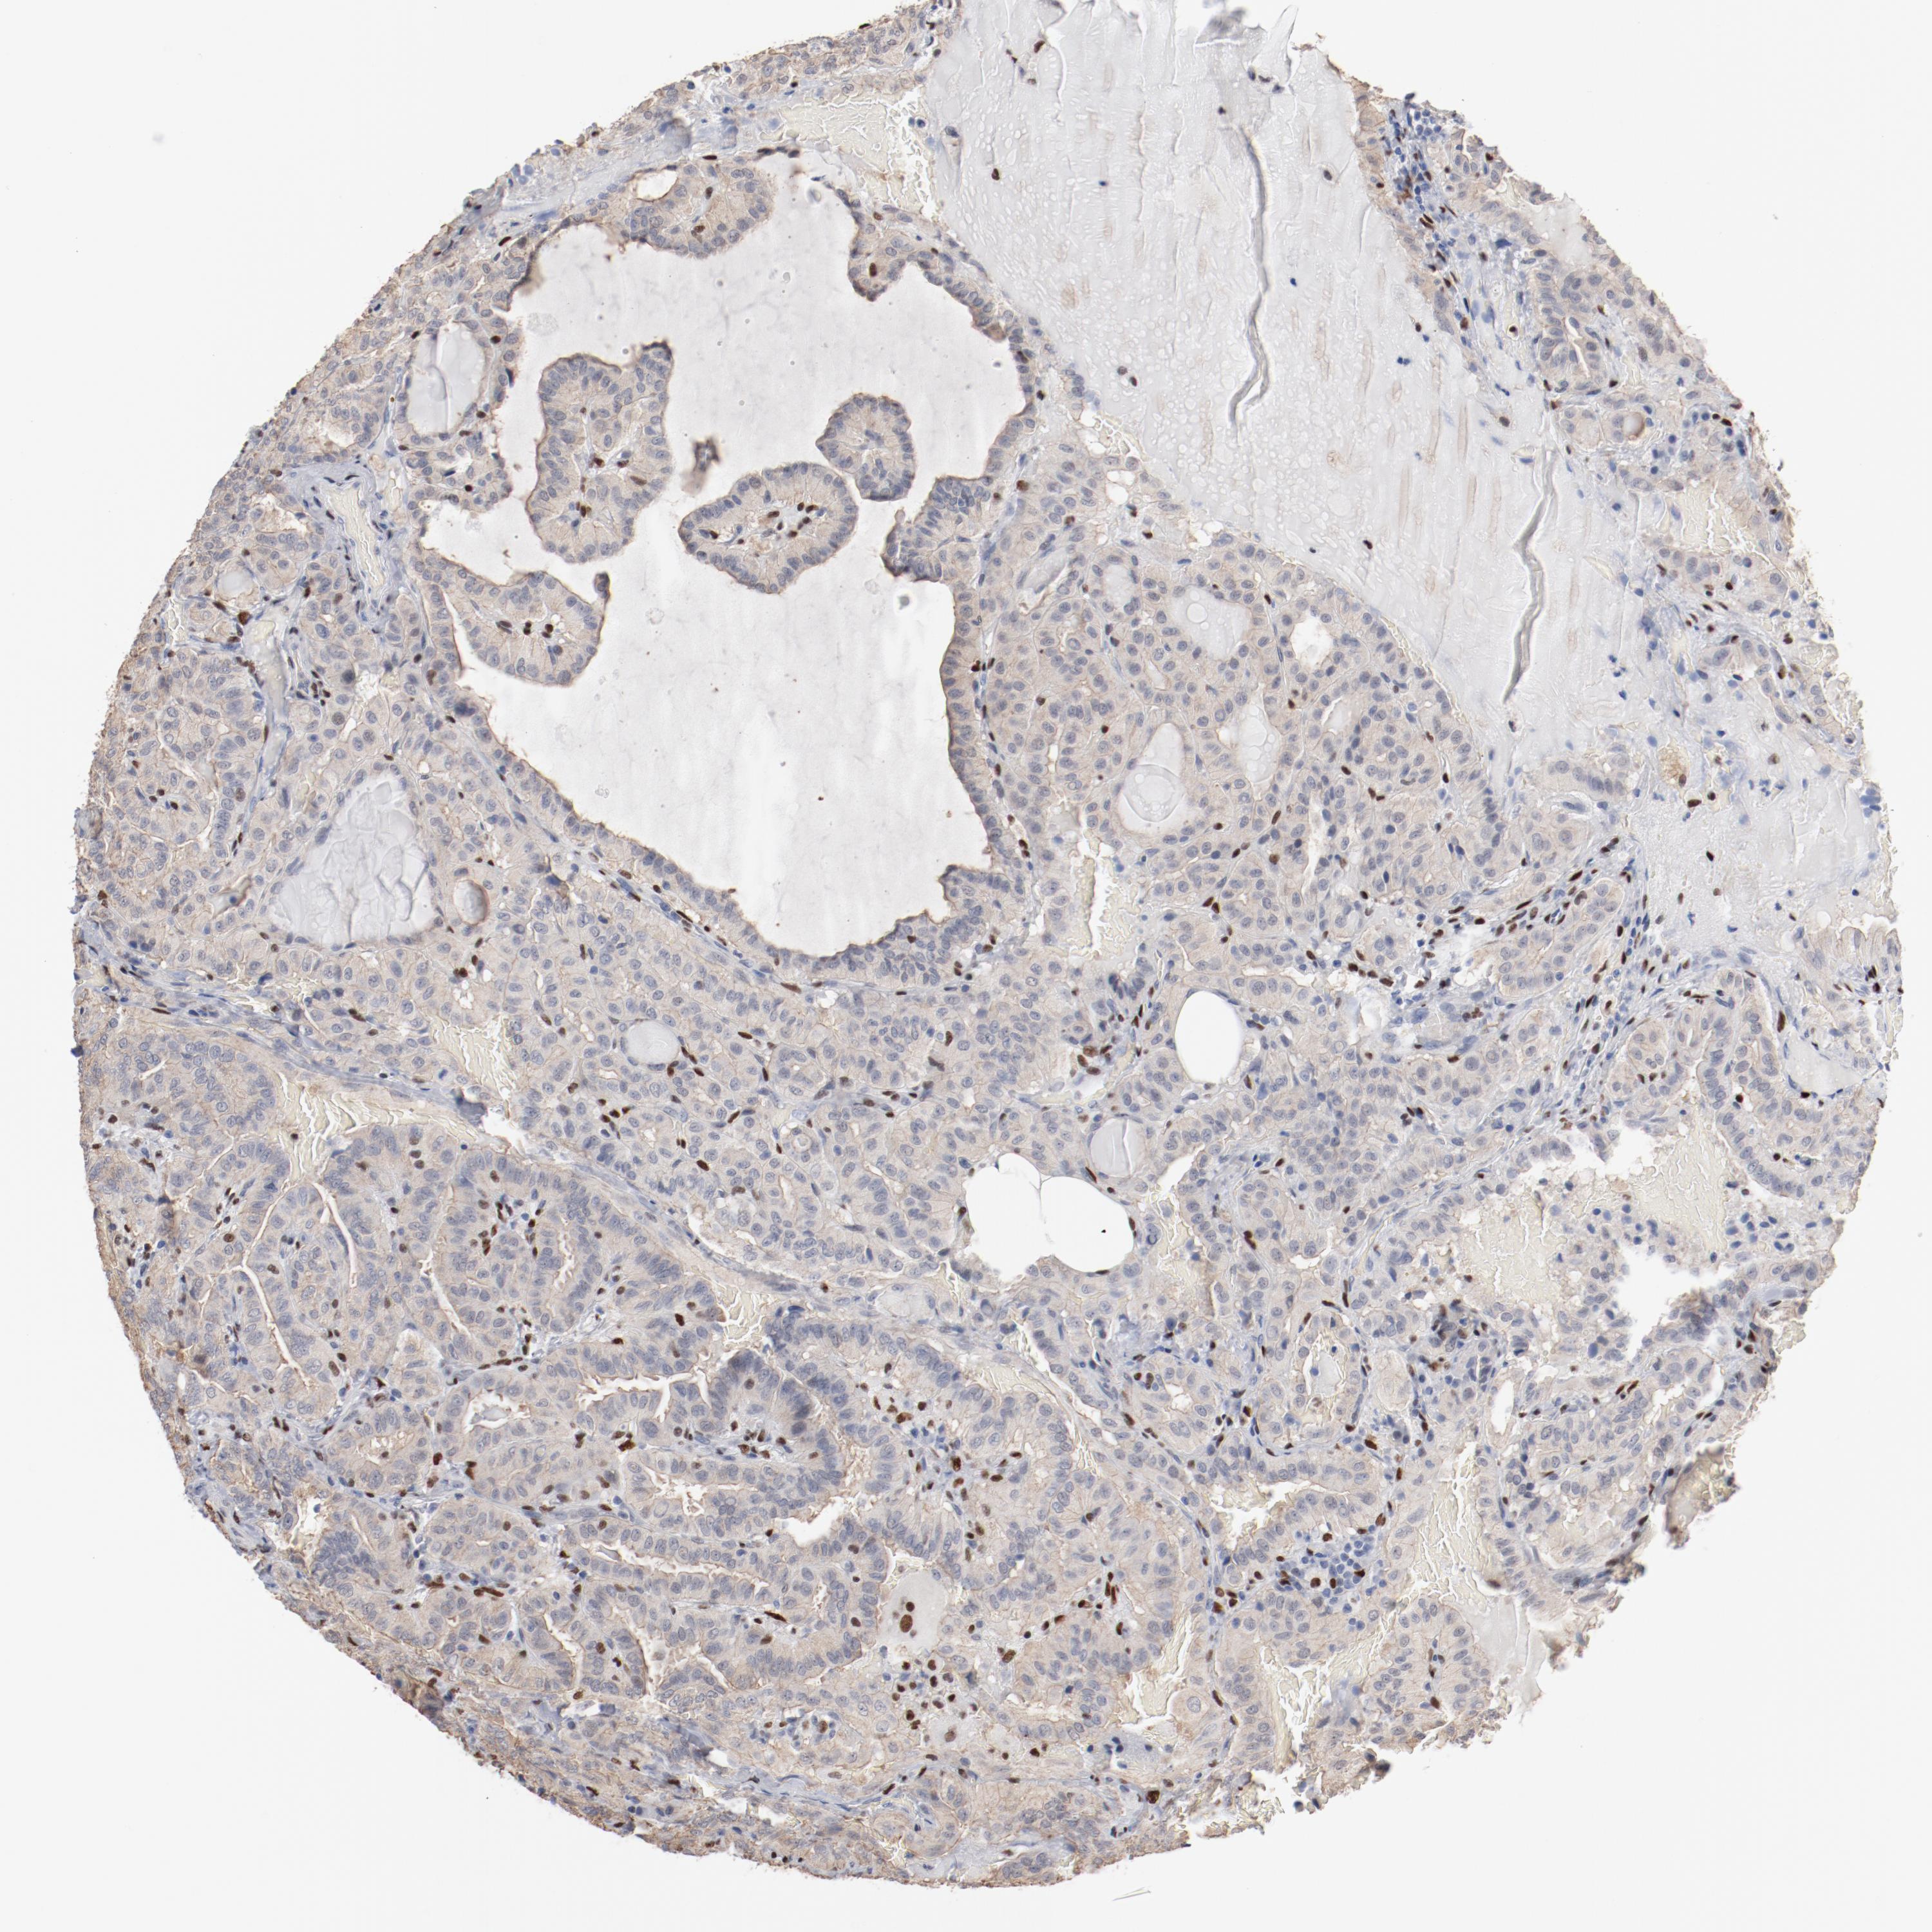

THYROID CANCER - Protein expressioni

A mouse-over function shows sample information and annotation data. Click on an image to view it in a full screen mode. Samples can be filtered based on level of antibody staining by selecting one or several of the following categories: high, medium, low and not detected. The assay and annotation is described here.

Note that samples used for immunohistochemistry by the Human Protein Atlas do not correspond to samples in the TCGA dataset.

Antibody stainingi

Antibody staining in the annotated cell types in the current human tissue is reported as not detected, low, medium, or high, based on conventional immunohistochemistry profiling in selected tissues. This score is based on the combination of the staining intensity and fraction of stained cells.

Each image is clickable and will lead to virtual microscopy that enables deeper exploration of all samples and also displays staining intensity scores, fraction scores and subcellular localization as well as patient and tissue information for each sample.

Antibody HPA003456

Staining

High

Medium

Low

Not detected

Intensity

Strong

Moderate

Weak

Negative

Quantity

>75%

75%-25%

<25%

None

Location

Nuclear

Cytoplasmic/membranous

Cytoplasmic/membranous,nuclear

Papillary adenocarcinoma, NOS

Carcinoma, NOS